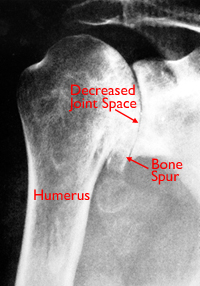

X-rays are imaging tests that create detailed pictures of dense structures, like bone. They can help distinguish among various forms of arthritis.

X-rays of an arthritic shoulder will show a narrowing of the joint space, changes in the bone, and the formation of bone spurs (osteophytes).

(Left) An illustration of damaged cartilage in the glenohumeral joint. (Right) This x-ray of the shoulder shows osteoarthritis and decreased joint space (arrow).

Illustration on left reproduced with permission from JF Sarwark, ed: Essentials of Musculoskeletal Care, ed 4. Rosemont, IL, American Academy of Orthopaedic Surgeons, 2010.

This x-ray shows severe osteoarthritis of the glenohumeral joint.

Reproduced with permission from Crosby LA (ed): Total Shoulder Arthoplasty. Rosemont, IL, American Academy of Orthopaedic Surgeons, 2000, p 18.